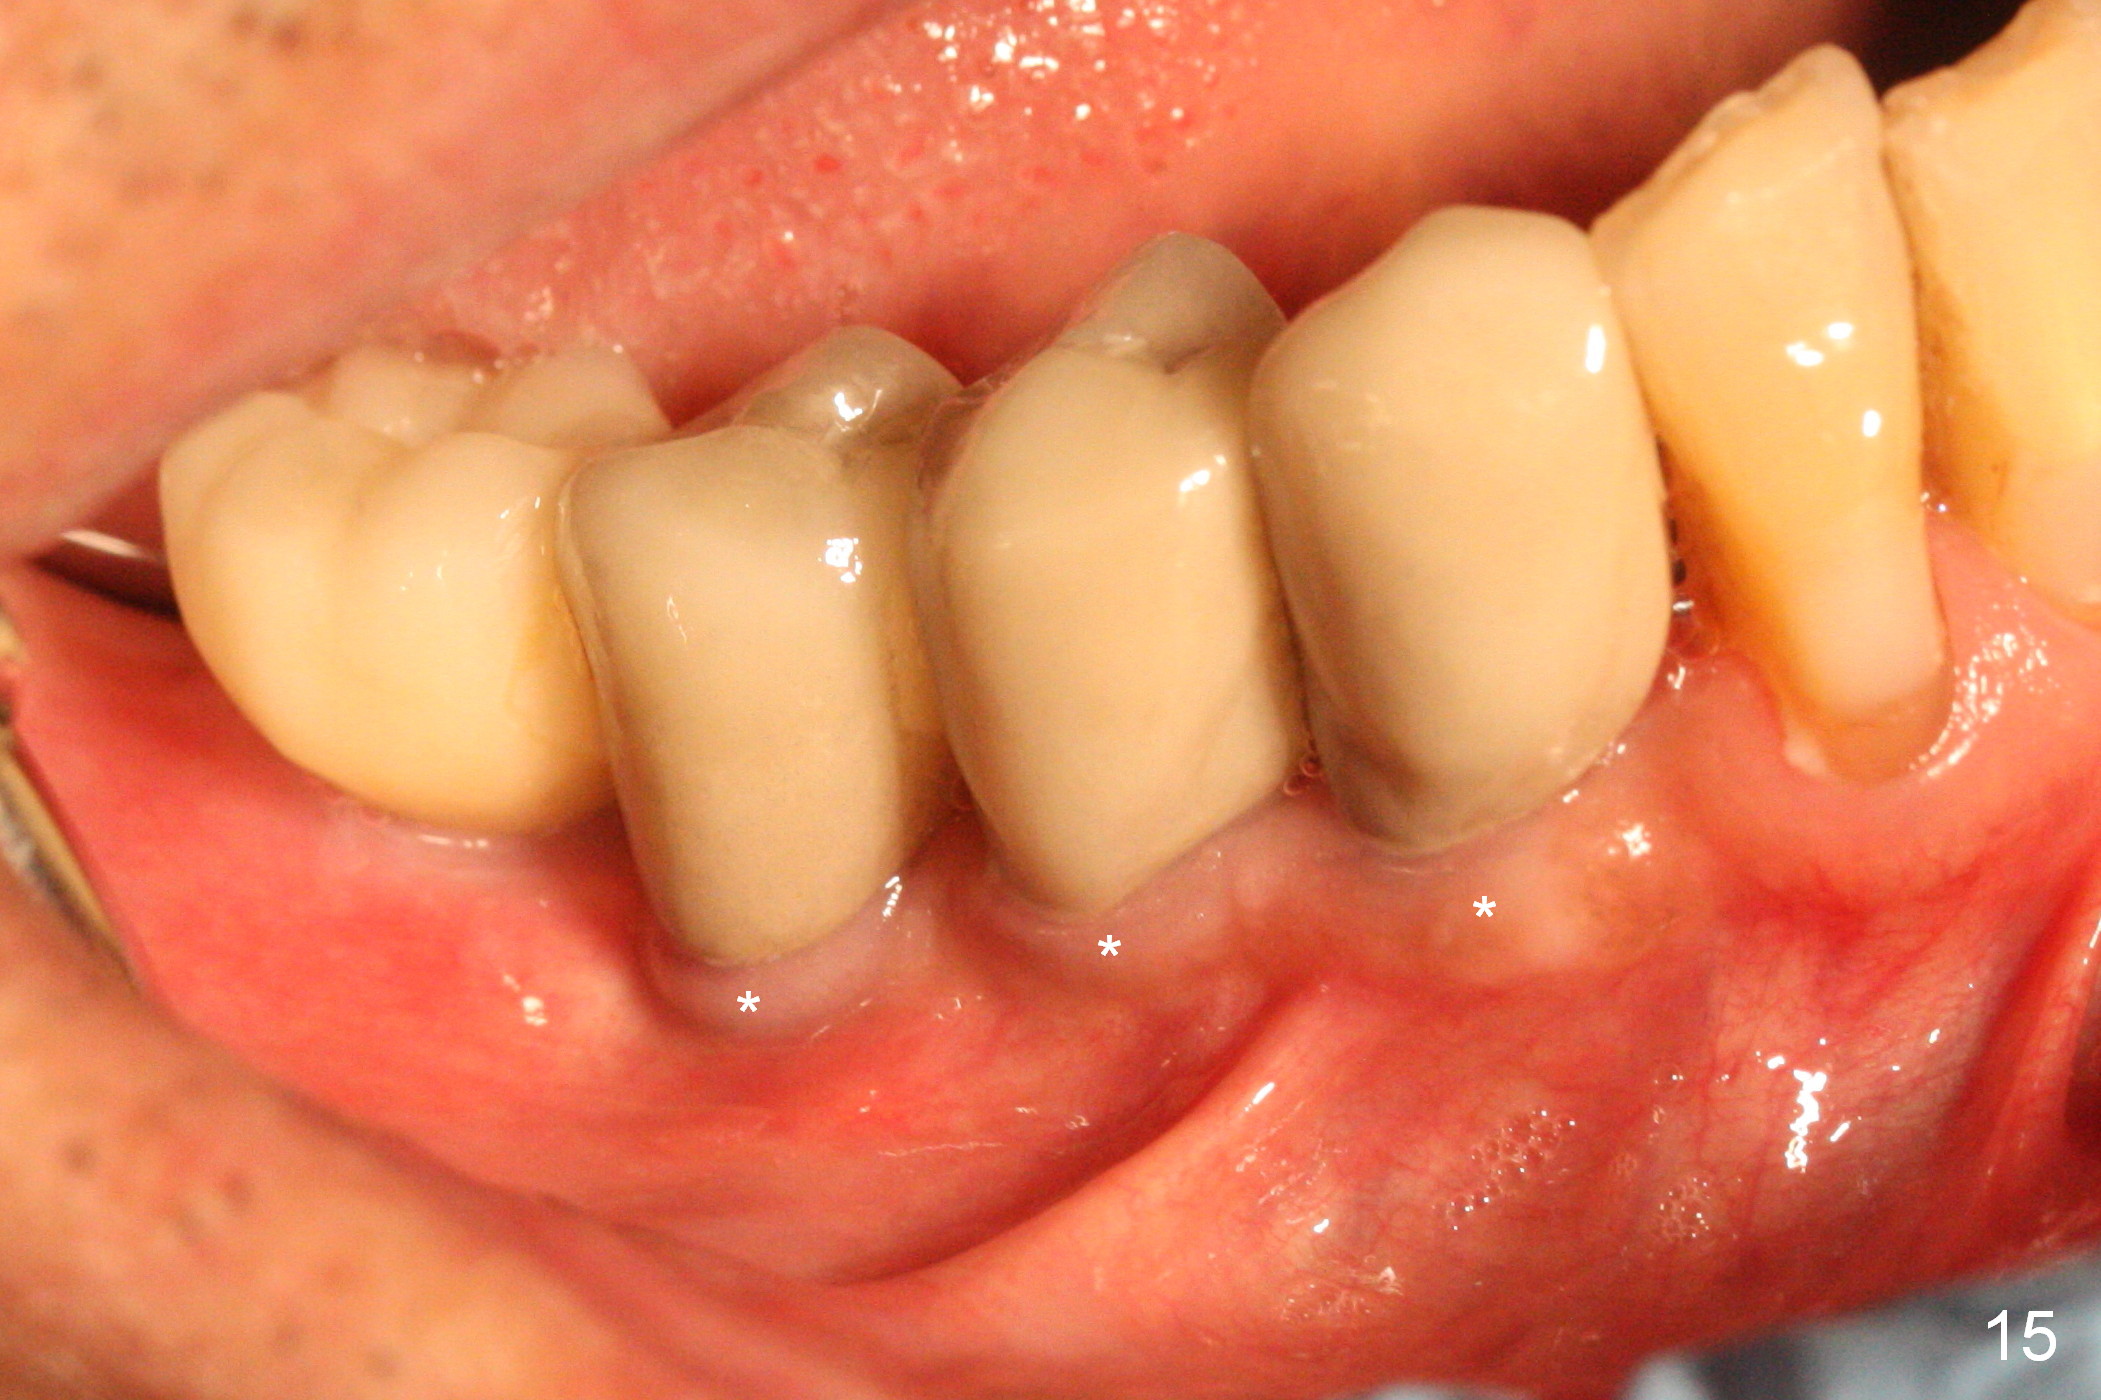

There appears to be no bone loss 2 years 5 months post cementation (Fig.14). Gingival bands form around the implants at #27-29 three years 1 month post cementation (Fig.15 *).